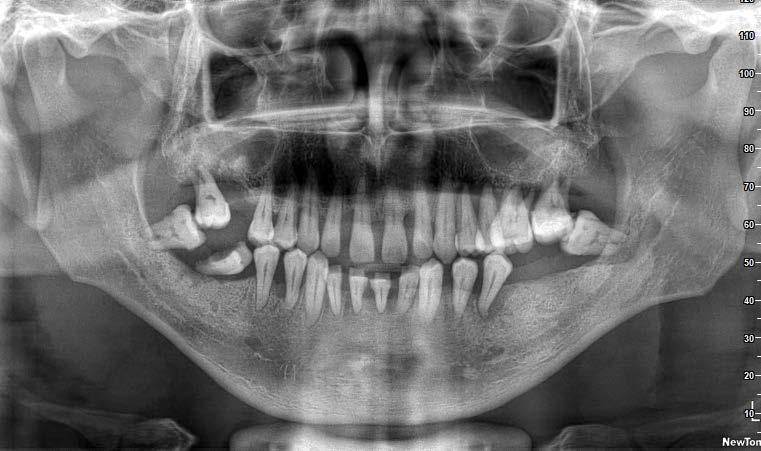

Caso clínico: paciente femenino de 19 años, patrón dolicofacial, perfil convexo, clase II esqueletal debido a una retrusión mandibular, mordida abierta anterior esqueletal, clase II molar, clase canina no establecida por mordida abierta, apiñamiento severo superior e inferior y deglución atípica.

Resultados: obtención de una clase canina I y clase molar II funcional, se corrigieron las sobremordidas horizontal y vertical, y se logró la coincidencia de líneas medias facial y dental. El manejo de la mordida abierta anterior se llevó a cabo por medio de la corrección del hábito de deglución atípica con la ayuda de spikes de resina, elásticos intermaxilares y arcos utility, y se obtuvieron buenos resultados estéticos, dentales y funcionales.